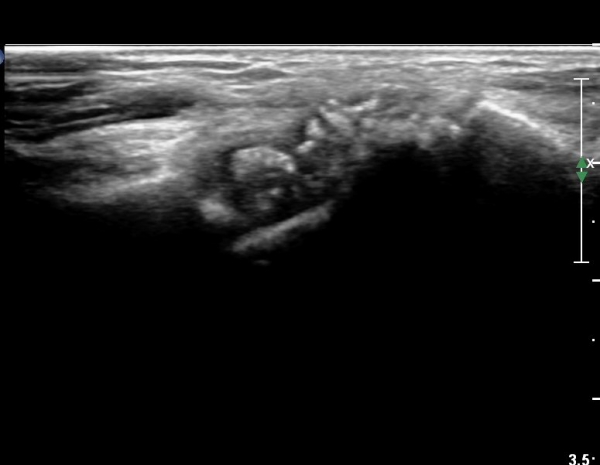

¼Õ¸ñ ºÎÀ§ Ⱦ´Ü¸é°Ë»ç¿¡¼ ¿ä°ñ°ú ¿ù»ó°ñ Àü¹æ¿¡ ¼®È¸È¼º À½¿µÀÌ Á¸ÀçÇϰí Àü¹ÝÀûÀÎ ¼öÁö ±¼°î°ÇÀÇ ºñÈÄ, Á¤Á߽ŰæÀÇ ºÎÁ¾°ú

ÈûÁÙ ¹× Á¤Á߽ŰæÀÇ Ç¥ÃþÀ¸·Î ÀüÀ§°¡ °üÂûµÈ´Ù, (»çÁø 1 ), ÆÄ¿öµµÇ÷¯°Ë»ç¿¡¼ Ç÷·ùÁõ°¡°¡ °üÂûµÊ´Ù(»çÁø 2)..